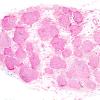

PERIPHERAL NEUROPATHY

15 NEUROPATHY ASSOCIATED WITH NEOPLASIA

2 Paraneoplastic Neuropathy (3)